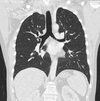

1

3

4